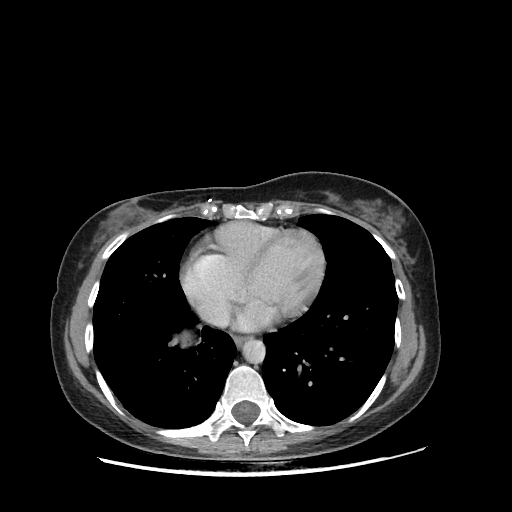

Original VENOUS CT scan

Full window (WL 1023.5, WW 4095 β†’ Low βˆ’1024, High +3071)

Mediastinum window (WL 40, WW 400 β†’ Low βˆ’160, High +240)